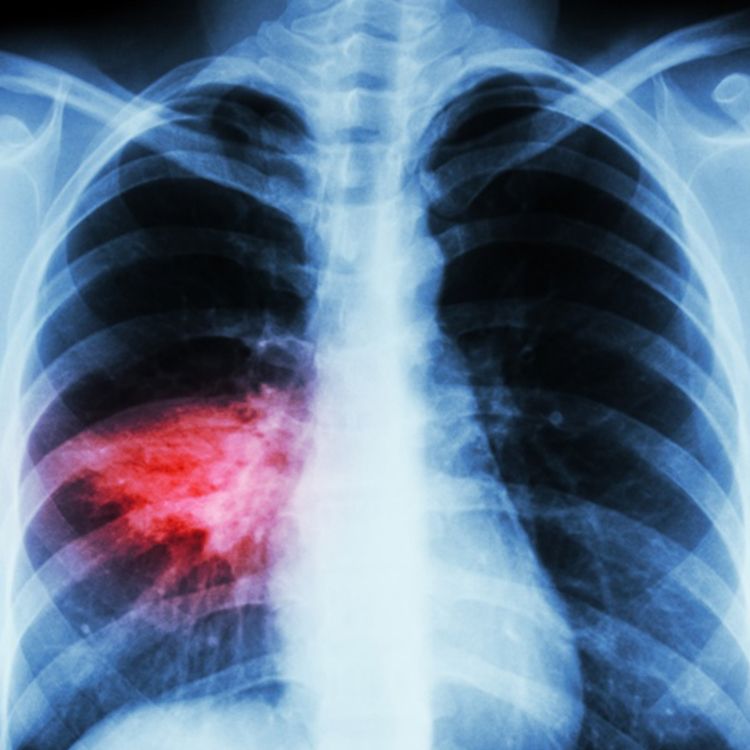

Pneumonia Causes, Signs, Symptoms, Shot & Pneumonia Treatment

Diagnosis of Pneumonia Does Pneumonia Cause Heartburn Chronic cough, bronchial asthma, bronchitis, pneumonia. cumulative incidence of pneumonia was significantly higher in the patients with gerd than that in the non. one thing you might not have thought about as a byproduct of gerd is pneumonia. gerd can cause various pulmonary manifestations: But wait, isn’t that a. respiratory reflux (lpr) is rarely recognized by. Does Pneumonia Cause Heartburn.